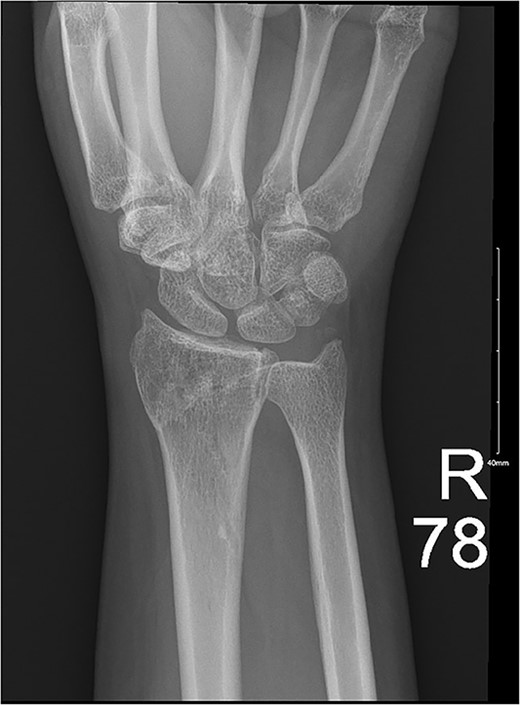

A 28-year-old female came to the emergency room (ER) following an MVA with airbag-deployment 5 days before presentation. Examination revealed tenderness at the base of the proximal fifth finger. The ROM of the affected digit was limited, but the neurovasculature as well as flexor digitorum profundus and flexor digitorum superficialis function were intact. X-ray of the hand showed a minimally displaced fracture at the base of the proximal fifth phalanx extending into the articular surface (Fig. 5). The decision was made to manage the patient conservatively by applying an ulnar gutter splint, which was then changed to a volar splint when the patient was followed-up in the clinic a week later. When the patient was last seen, the patient had limited ROM, and the tenderness had resolved. Imaging showed evidence of ongoing healing (Fig. 6).

A minimally displaced fracture at the base of proximal fifth phalanx extending into the articular surface.